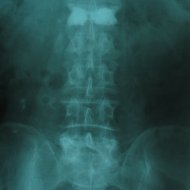

Kemik Erimesine (Osteoporoz) Bağlı Omurga Kırığı: İleri yaşta osteoporoz, yaşlılık ve/veya menopoza bağlı kemik kitlesinin azalması nedeniyle oluşur. Kemikleri zayıflatan bu sorun nedeniyle basit travmalarda bile kemikler kırılabilir hale gelir. En çok kırılan kemikler omurga ve kalça kemikleridir. Osteoporozun çok ileri olduğu bazı durumlarda hasta aksırınca bile omurgası kırılabilir. Bu durumda hastaya kemik çimentosuyla dolgu tekniği (vertebroplasti) uygulanabilir. Ancak tekrarlayabileceği göz önünde bulundurularak kemik erimesine yönelik ilaç tedavisi unutulmamalıdır. Hastalarda en sık ortaya çıkan şikayet sırt ya da bel ağrısıdır. Bazen çökme kırıkları sonucu olan ağrı hastayı çok rahatsız etmez ama oluşan deformite sonucu hasta doktora başvurur. Yaşlılarda Kifoz: Yaşlanan omurgada hem osteoporotik kırıklar hem de disklerde oluşan dejenerasyonla beraber kifoz oluşabilir. Bu durum bir yandan hastada solunum sorunları oluştururken diğer yandan günlük aktiviteleri kısıtlar. Yaşlılarda Skolyoz: İleri yaşta skolyoz ya dejeneratif omurga sorunları sonucunda ya da geçmişte var olan skolyozun artmasıyla oluşabilir. Birinci durum sinirlere bası nedeniyle sıklıkla bacaklara yayılan ağrı ile beraberdir.

Kemik erimesine (osteoporoza) bağlı omurga kırığı olan hastada vertebroplasti (çimento ile dolgu) tedavisi